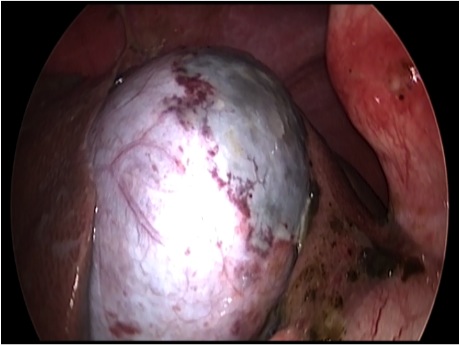

胆嚢が破裂した様子を腹腔内にカメラを入れて観察した像です。

胆嚢から漏れ出た胆汁が腹腔内に確認できます